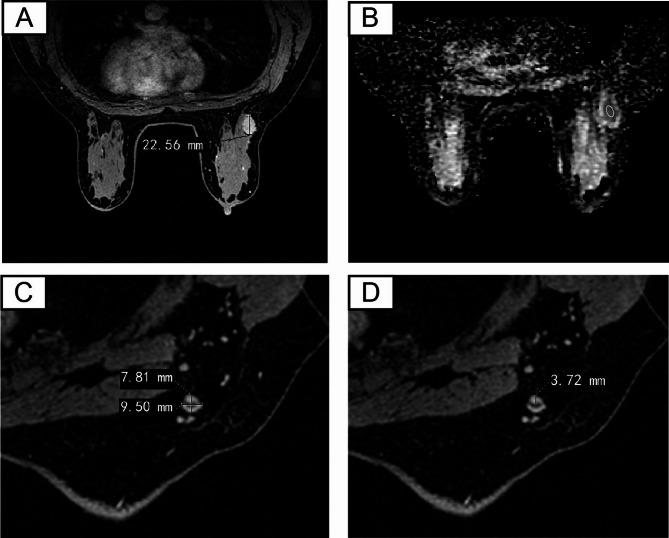

A non-invasive preoperative model for predicting sentinel lymph node metastasis in breast cancer using clinical data and MRI.